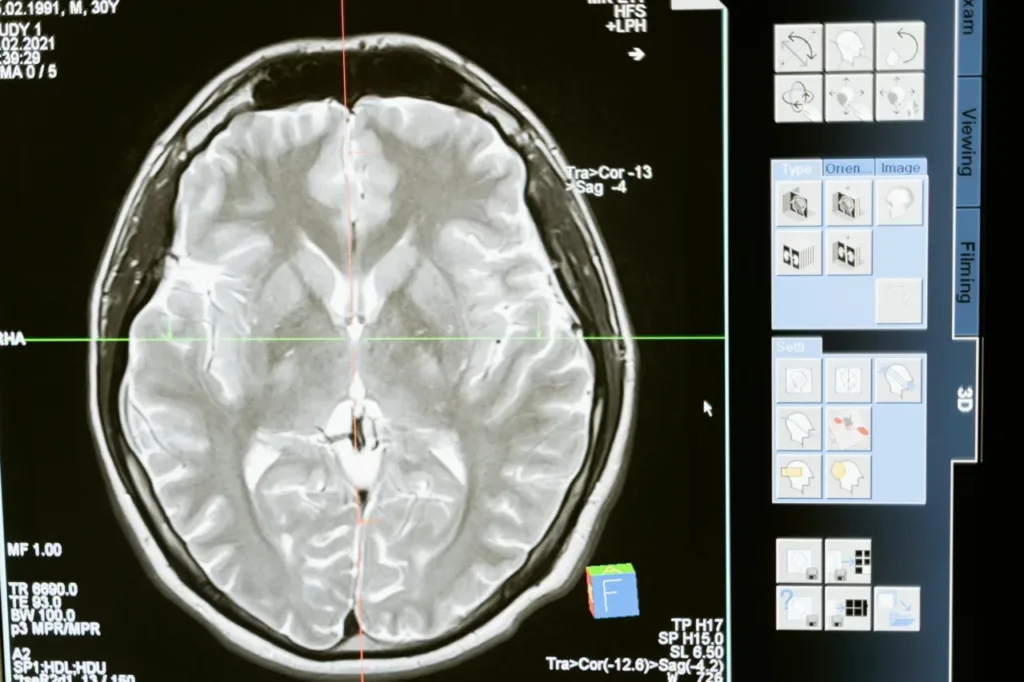

Diagnostic imaging, especially neonatal MRI, and continuous EEG are central to prognosis and to legal case building. High quality imaging that correlates with clinical signs can be decisive evidence in an HIE Brain Injury Settlement when demonstrating timing and severity of injury.

Establishing causation requires connecting the negligent act to the timing and pattern of brain injury. Magnetic resonance imaging that shows watershed or basal ganglia injury consistent with peripartum hypoxia, low cord blood gases, severely low Apgar scores, and placental pathology provide objective linkage. Expert testimony integrates these data with the clinical timeline to show that, but for the breach, the hypoxic event would likely have been avoided or mitigated, which supports quantifying damages in an HIE Brain Injury Settlement.

High-resolution imaging, with expert interpretation, links clinical events to patterns of hypoxic injury on MRI or ultrasound. Use clear demonstrative exhibits and animations to show injury mechanisms, prognosis, and cost projections, they make complex data accessible to juries and adjusters, and they strengthen demand packages for an HIE Brain Injury Settlement.

Proving an HIE birth injury claim requires comprehensive hospital records (labor and delivery notes, fetal heart tracings, medication logs), neonatal records, and diagnostic imaging such as MRI showing hypoxic-ischemic injury. Expert testimony from obstetricians, neonatologists, and pediatric neurologists is essential to link the injury to a deviation from the standard of care and to establish causation and prognosis. Documentation of ongoing care needs, therapy records, and life-care planning help quantify damages. Chain-of-custody for records and timely preservation of fetal monitoring strips are often critical evidentiary elements.